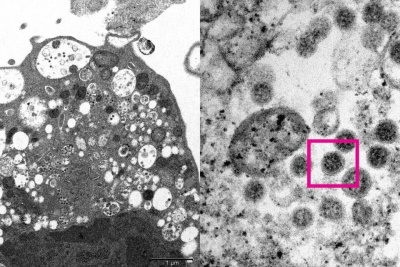

Новый штамм коронавируса «омикрон» отличается легким течением заболевания, но имеет быстрый темп распространения. Об этом в ходе прямого эфира сообщила главный внештатный инфекционист министерства здравоохранения Якутии, заведующая кафедрой инфекционных болезней, фтизиатрии и дерматовенерологии медицинского института СВФУ им. М.К. Аммосова Снежана Слепцова, передает ЯСИА.

«Штамм «омикрон» отличается достаточно легким течением заболевания, но является очень контагиозным вирусом. Он быстро распространяется, что может вызвать очень большую перегрузку системы здравоохранения. Поэтому от всех нас требуется бдительность: необходимо соблюдать все те меры защиты здоровья, которые были при прежних штаммах коронавируса»,  — сказала Снежана Слепцова.

Врач отметила, что в отличии от «дельта» штамма коронавируса «омикрон» в первую очередь поражает иммунную систему.  Симптомы заболевания могут быть самыми разными: начиная от обычного недомогания, заканчивая температурой, насморком, боли в горле, заканчивая кашлем и слабостью. Между тем, потеря обоняния встречается лишь в 1/4 случаев заболевания.